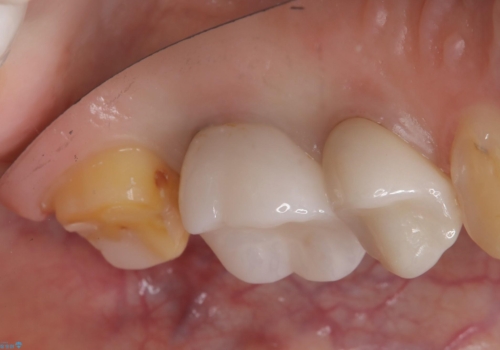

- 二次う蝕が心配という主訴で来院された患者さんです。

保険のメタルインレーは腐食しやすかったり、適合があまり良くなかったりで二次的にう蝕がインレー下で広がってしまうことが多々あります。

メタルインレーを除去したところ、残存歯質量が少なく破折のリスクを説明し、ゴールドクラウンでのやり替えとなりました。